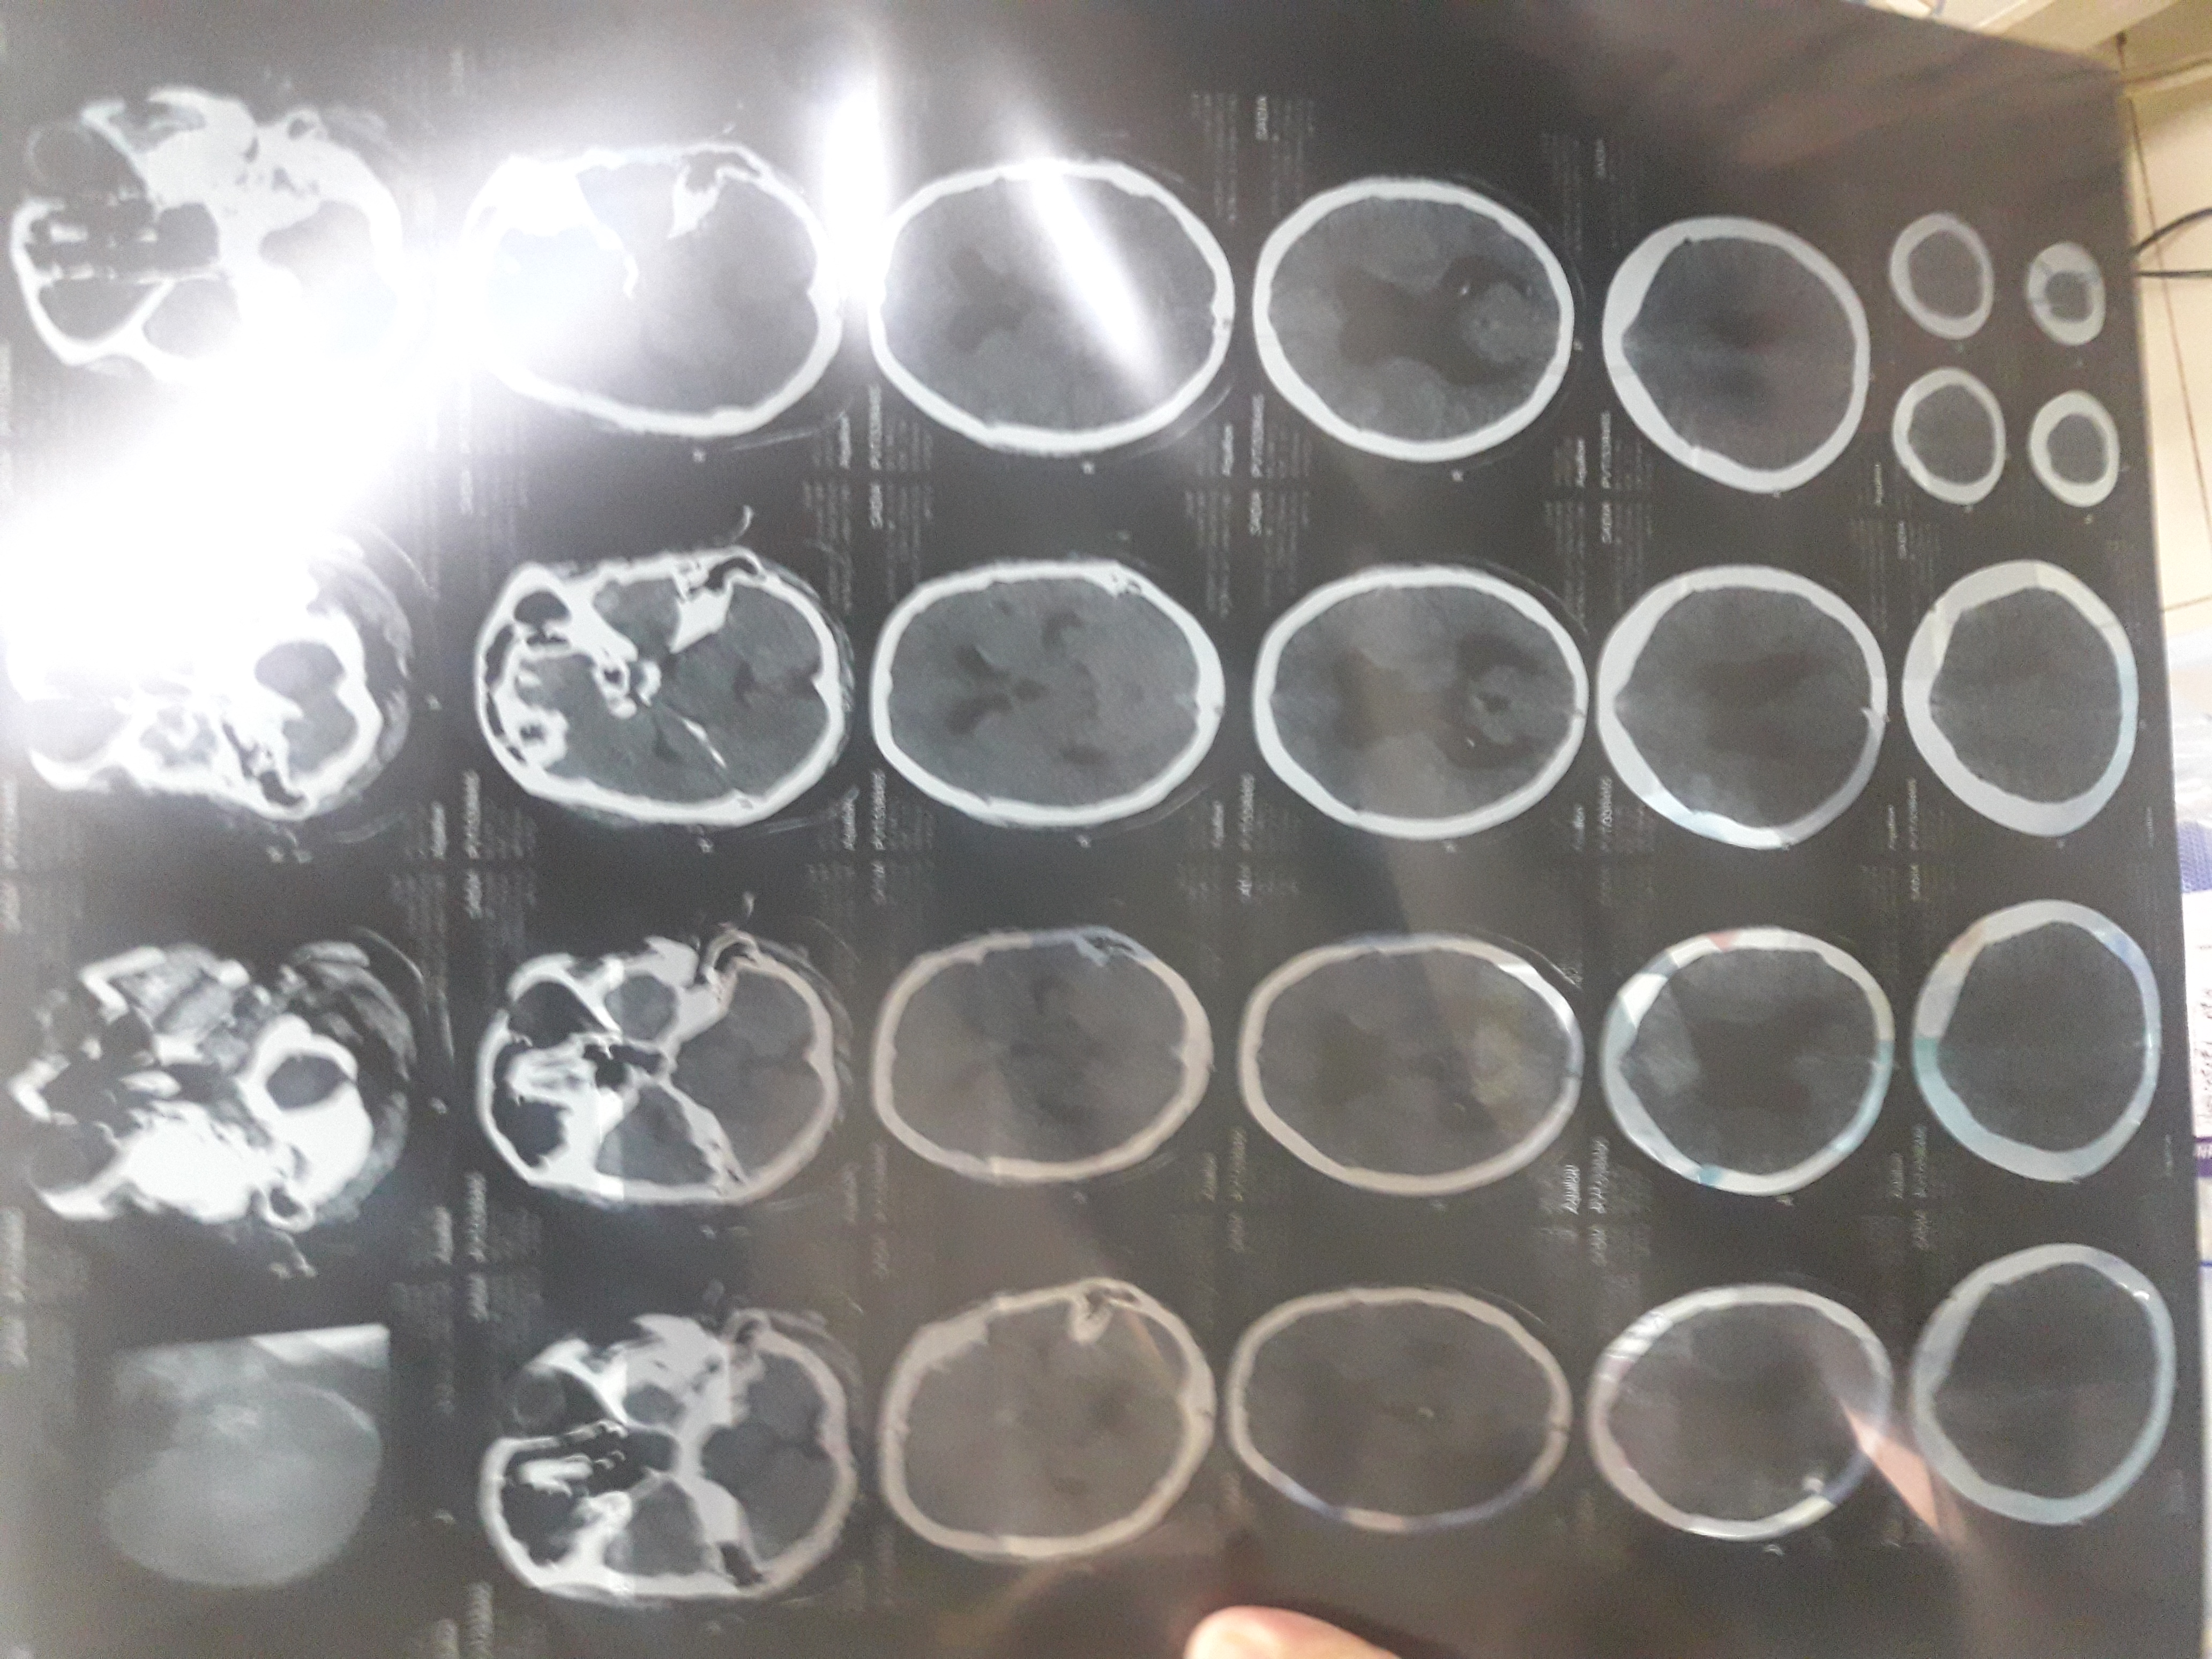

Asking for Sister, Female, 29 years old, Swabi

Aslamghalaikom dear drs meray behan 17.6.2018 ramzan mien oskay bachay shore kar rahay thay to wo osko gussa jiki waja say oskay sirko chot phoncha nas demage ho gaya doctors ko dakya to koi fayeda nhi howa aur sir osi tarah dard hai hum nay vp shunt kiya lkn abhi hosh mein nhi ati 40 days hogien oskay na kuch bhol sakti hai na harkat karsakti hai aur na kuch ka pe sakti haiso plz koi mashwarah day day k hum mazeed kya karay q k ham sub bohut pareshan hai aur kafi pasay b laga dayien

Attach Photo here: